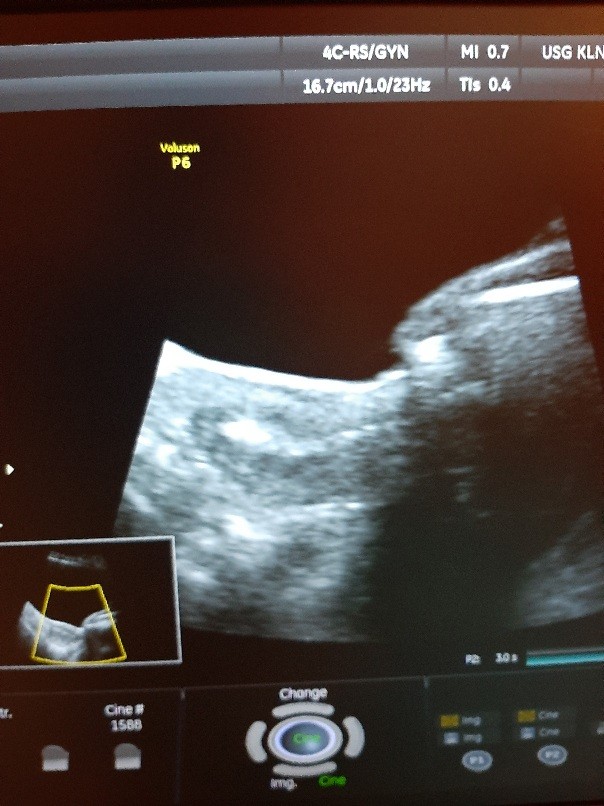

Ja juz z kropkiem w brzuszku 😍😍😍 piekny jest 😊

Załączniki

• 20210312_144045.jpg

20210312_144045.jpg

107,8 KB · Wyświetleń: 99